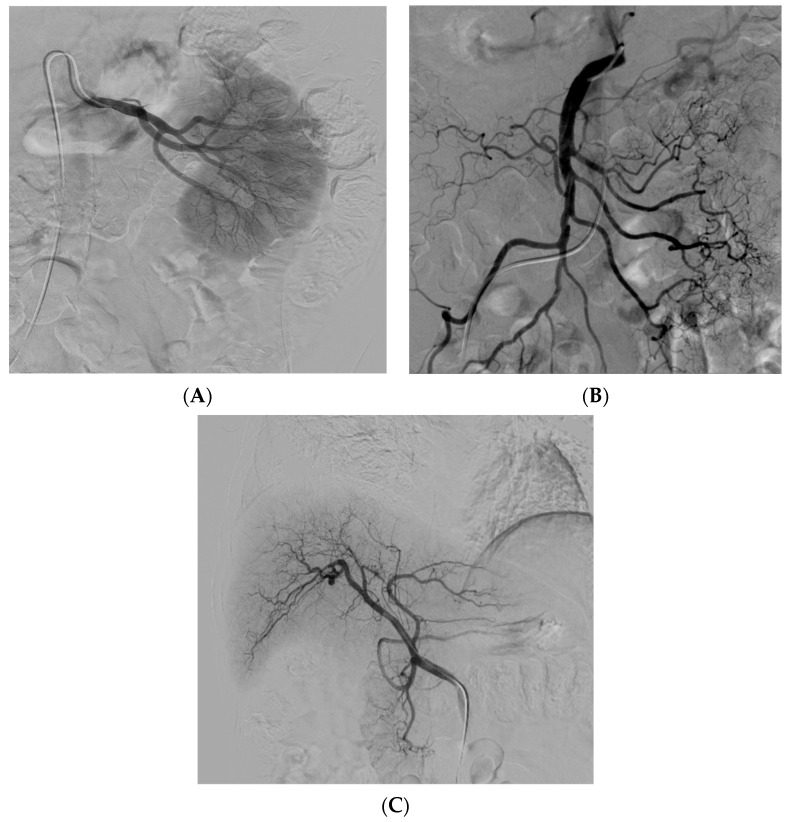

經(jīng)動(dòng)脈干細(xì)胞注射(TASI)可能被認(rèn)為是一種理想的選擇性遞送方法,在所需器官中具有最佳分布和高干細(xì)胞濃度。在組織取樣和干細(xì)胞分離處理(自體或異體)之后,該過(guò)程基本上包括通過(guò)動(dòng)脈通路(最常見(jiàn)的是股動(dòng)脈)引入導(dǎo)管。然后,在熒光鏡和造影劑引導(dǎo)下,將導(dǎo)管放置在所需的供血?jiǎng)用}(肝動(dòng)脈、腸系膜動(dòng)脈或腎動(dòng)脈)中,以進(jìn)行隨后的干細(xì)胞注射。圖2)。

圖2:腎 (?A?)、腸系膜上動(dòng)脈 (?B?) 和肝動(dòng)脈 (?C?) 的血管造影插管

導(dǎo)管定位確保對(duì)所需組織進(jìn)行選擇性治療,避免非目標(biāo)干細(xì)胞輸注。